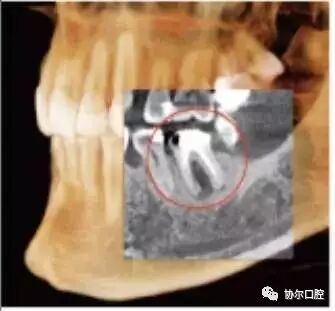

口腔锥形束CT

Quantum iQ的专利图像处理技术提供平滑的软组织影像,并最大程度的显示硬组织和骨结构的细节及对比。

Quick Scan模式 下,扫描在4.8秒内即可完成,以更小的放射剂量快速生成大量图像。

i-PAN功能,利用一项独一无二的专利使KaVo 3D eXam i成为一个功能上二合一的系统,不仅可以获取3D影像,而且可以获取常规2D全景图像。

i-Collimator(准直器) 能限制X射线辐射范围,仅扫描预先选定的区域,并且控制视野外的照射剂量。

人体工程学稳定系统 (ESS) 通过可调节座椅控制,有力的头部固定和稳定系统设计,最大程度的增加患者在扫描过程中位置的稳定性和准确性。

最全面的诊疗解决方案

完整的骨结构TMJ分析

真实可靠的牙周影像

强大的3D正畸分析

高质量的牙体牙髓

精确的气道分析

专业的种植与修复设计

一句话,使用KaVo 3D eXam i独有的软件可以准确而高效地实现对种植、基台、修复体的设计,帮助种植、修复、牙体牙髓以及正畸计划的制定和实施。完整的骨结构TMJ分析,精确的气道分析是很多三合一CBCT达不到的,也是医生在诊断中容易忽视的。工欲善其事,必先利其器,好的影像学检查资料,将为医生的治疗锦上添花。